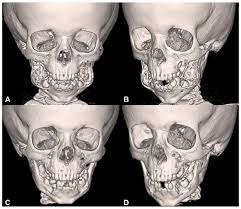

Cherubism In A 4 Year Old Boy Managed With Tumor Curettage Mandibular Osteotomies And Repositioning

Cherubism In A 4 Year Old Boy Managed With Tumor Curettage Mandibular Osteotomies And Repositioning from oaepublishstorage.blob.core.windows.net

In most patients, cherubism is due to dominant mutations in the sh3bp2 gene on chromosome 4p16.3. Cherubism is a disorder characterized by abnormal bone tissue in the jaw. Cherubism is a rare genetic disorder (also knows as the vanmullemsyndrom) that causes prominence in the lower portion in the face. A hereditary condition characterized by swelling of the jawbones and especially in young children by a characteristic facies marked by protuberant cheeks and upturned eyes learn more about cherubism dictionary entries near cherubism Cherubim/cherubs are angelic beings involved in the worship and praise of god. The term cherubism was invented in 1933 by jones, who linked the full cheeks and the orbital displacement with the round faces and heavenly directed gaze of renaissance cherubs. A cherub, or known in the plural form as cherubim, is a symbolical angelic figure repeatedly mentioned in the bible.cherubim are described as serving the will of god, performing divine duties in the earthly realm. © 2003 by saunders, an imprint of elsevier, inc. Affected children appear normal at birth. Cherubism is characterized by having painless bilateral enlargement of an individual's jaws whereby fibrous tissue replaces the bone. Cherubism is a rare disorder and the precise incidence is unknown. Approximately 200 cases have been reported by medical journals, most of which are men. Cherubism is a rare autosomal dominant disease of the jaw and maxilla.

The appearance of people with the disorder is caused by a loss of bone in the jaw that the body replaces with excessive amounts of fibrous tissue. Cherubism (omim #118400) is a rare autosomal dominant bone disorder characterized by symmetrical expansion of the jaws where giant cell lesions replace the bone. The cherubim are first mentioned in the bible in genesis 3:24, after he drove the man out, he placed on the east side of the garden of eden cherubim and a flaming sword flashing back and forth to guard the way to the tree of life. © 2003 by saunders, an imprint of elsevier, inc. Medical definition of cherubism :

Medical definition of cherubism : Cherubism is an autosomal dominant disorder that may be related to tooth development and eruption. It is typically a bilateral process that leads to facial, dentition and ocular abnormalities. © 2003 by saunders, an imprint of elsevier, inc. Typically, cherubism is an isolated benign condition; Cherubism is a rare disorder and the precise incidence is unknown. Cherubism (omim #118400) is a rare autosomal dominant bone disorder characterized by symmetrical expansion of the jaws where giant cell lesions replace the bone. Approximately 200 cases have been reported by medical journals, most of which are men.

In most patients, cherubism is due to dominant mutations in the sh3bp2 gene on chromosome 4p16.3. Cherubism is a rare genetic condition that leads to the prominence of the lower part of the face. Cherubism is a rare autosomal dominant disease of the jaw and maxilla. Through the influence of the septuagint, cherubim was used in the earlier english versions, also as a singular, hence, the plural was made to sound cherubims. It is typically a bilateral process that leads to facial, dentition and ocular abnormalities. Affected children appear normal at birth. Interestingly, penetrance is dependent on gender: Cherubim/cherubs are angelic beings involved in the worship and praise of god. A hereditary condition characterized by swelling of the jawbones and especially in young children by a characteristic facies marked by protuberant cheeks and upturned eyes learn more about cherubism dictionary entries near cherubism The disease was first reported in 1933 1. Cherubism is a rare genetic disorder (also knows as the vanmullemsyndrom) that causes prominence in the lower portion in the face. Cherubism is a rare genetic condition that affects the bones of your lower jaw and sometimes upper jaw. © 2003 by saunders, an imprint of elsevier, inc.

Cherubism is a disorder characterized by abnormal bone tissue in the jaw. A cherub, or known in the plural form as cherubim, is a symbolical angelic figure repeatedly mentioned in the bible.cherubim are described as serving the will of god, performing divine duties in the earthly realm. © 2003 by saunders, an imprint of elsevier, inc. Cherubism, a clinicopathological entity of genetic origin, predominantly affects the mandible, with maxillary involvement to a lesser degree. Cherubism is a rare autosomal dominant disease of the jaw and maxilla.